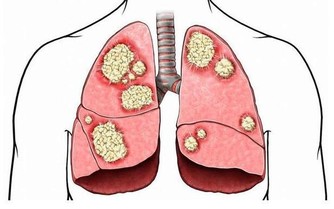

當你出現肺炎的症狀後,如發熱、咳嗽、喘不上氣等,需要盡快去醫院就診,聽診器可以初步判斷你是否肺部有病變,而此外,你可能會需要抽血化驗、胸部影像檢測、脈搏血氧檢查和痰液檢查來確診是否患有肺炎。

而本次新型冠狀病毒會導致肺炎的發生,如果你有類似流感的症狀,醫生會建議你通過核酸檢查,來判斷是否感染了這種病毒。